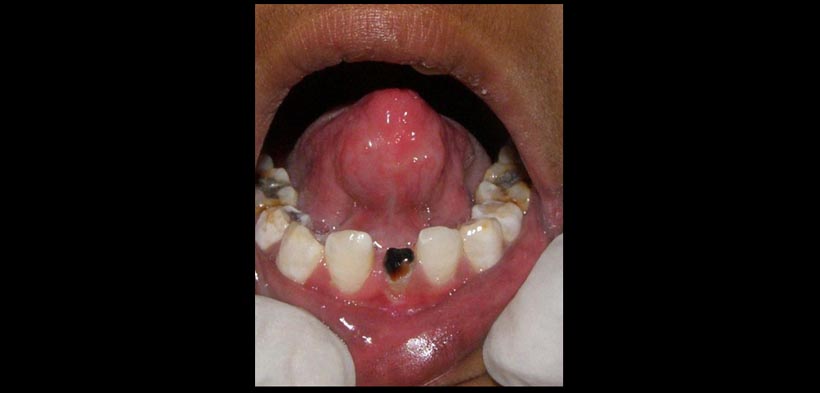

- Una variante muy rara es la anquiloglosia en el cual existe fusión del frenillo lingual con el frenillo labial mandibular, esta entidad se ha reportado en un niño asociado con oligodoncia de la dentición molar temporal. En el presente caso, anquiloglosia se asoció con anodoncia parcial del sector de los dientes permanentes del sector antero inferior.

La anquiloglosia es la restricción de movimiento de la lengua debido a una anomalía congénita en el frenillo lingual, es necesario saber la etiología, las implicancias clínicas y alternativas de tratamiento de esta afección para su adecuado manejo. Se presenta un caso de un tipo inusual de anquiloglosia que no puede ser clasificado utilizando el sistema de clasificación actual de anquiloglosia, en el que sólo la punta de la lengua se fusiona con el frenillo labial del arco mandibular y se asocia con la falta de dientes permanentes en el sector antero inferior, se sugiere mayores estudios de correlacion con respecto a la perdida prematura de dientes o ausencia congénita de dientes en el sector antero inferior y la posible causa de que puedan agravar la anquiloglosia.

Fig. 1. Anquiloglosia; fusión de la punta de la lengua con el frenillo bucal en un paciente pediátrico con oligodoncia de los incisivos anteroinferiores.